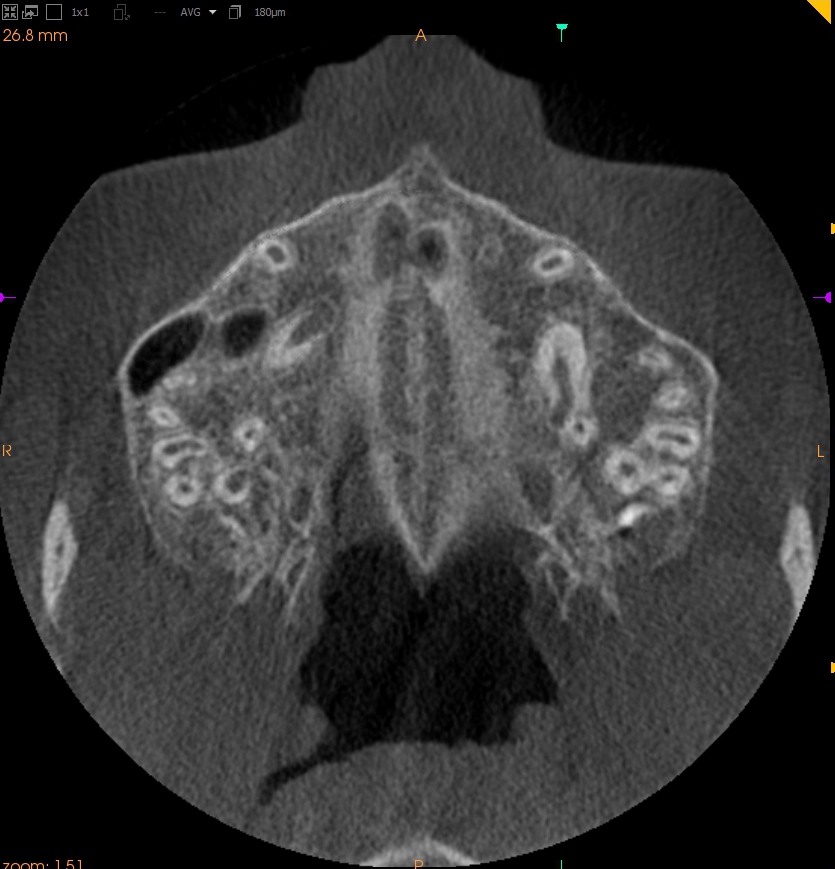

Resorpcja zęba to proces powstania ubytku twardych struktur zęba wywołanego przez osteoklasty bez kontaktu ze środowiskiem jamy ustnej, między innymi na skutek ucisku wywieranego przez ząb zatrzymany. Dla lekarza ortodonty jest istotne ustalenie, czy zęby zatrzymane lub twory nadliczbowe powodują resorpcję zębów stojących w łuku w celu wczesnej eliminacji przyczyny resorpcji. Celem pracy jest przedstawienie opisu przypadku zastosowania tomografii stożkowej w diagnostyce nieprawidłowo położonych zawiązków zębów przedtrzonowych drugich górnych. Stwierdzono, że tomografia stożkowa jest skuteczną metodą oceny wczesnej resorpcji zewnętrznej korzeni zębów.

Tooth resorption is the process of appearing of a defect of hard tissues of teeth caused by osteoclasts not having contact with oral cavity environment, eg. due to mechanical pressure exerted by an impacted tooth. It is essential for an orthodontist whether impacted teeth or supplementary teeth cause resorption of erupted teeth in order to early eliminate the causative factor of the resorption. The aim of the paper is to describe a case report of cone-beam computed tomography (CBCT) in diagnostics of incorrectly located germs of upper second premolars. It was found that CBCT was an efficient method of imaging of early external root resorption.